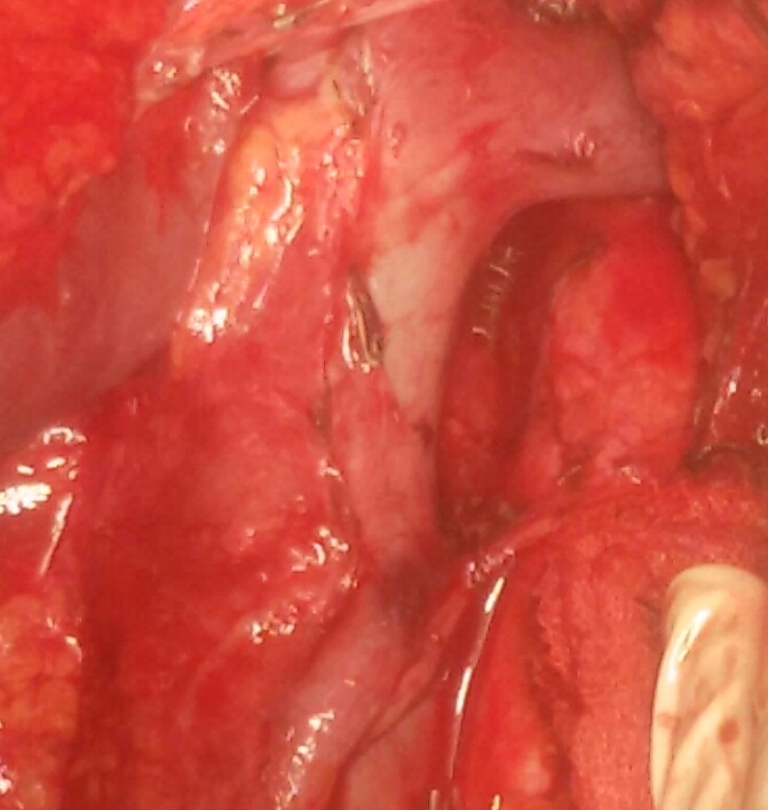

Першочерговою моєю ціллю була операційна, де інтенсивну програму забезпечував молодий та надзвичайно талановитий завідувач відділення Даніель Піндяк, за спиною якого багато закордонних стажувань та визнання як одного з кращих онкохірургів цієї країни. Власне завдяки йому в мене була можливість розширити свої знання в галузі сучасних стандартів онкологічних розширених лімфодисекцій при раку шлунка та підшлункової залози. Складність оперативних втручань, які він виконує, говорить сама за себе: панкреатодуоденальні резекції, RAMS, гастректомії з D2 лімфодисекцією та розширеною лімфодисекцією, дистальні та тотальні резекції стравоходу, судинні реконструкції при місцево-розповсюджених процесах, резекції печінки, широкі заочеревинні лімфаденектомії та багато інших.

Деякі з таких оперативних втручань виконуються і в нашому хірургічному відділенні Тернопільської університетської лікарні. Проте кожне нове стажування і асистування під час подібних операцій за кордоном додають нового досвіду і суттєво покращують навички.